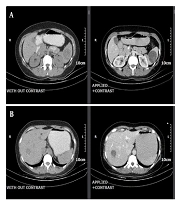

Hydatid Cyst Disease of the Thyroid Gland: A Rare Case Report